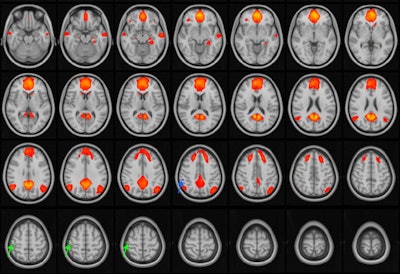

Functional MRI (fMRI) shows that adolescents and young adults who have sustained three to five concussions have disrupted brain connectivity in their default mode network, according to study results being presented at the RSNA 2021 meeting in Chicago.

The default mode network is activated when people are daydreaming, thinking of the future, or recalling memories, a team led by Dr. Thomas Johnson, PhD, of the University of Rochester Medical Center in New York. This network crosses the medial prefrontal cortex, the posterior cingulate cortex, the inferior parietal lobule, the temporal cortex, and the hippocampus. Changes to the network are associated with a range of diseases and disorders.

The researchers found no differences in connectivity in the default mode network in patients who had one or two concussions compared with healthy controls. But those who had a history of three to five concussions did have disruptions in the network that were not seen in those who did not.